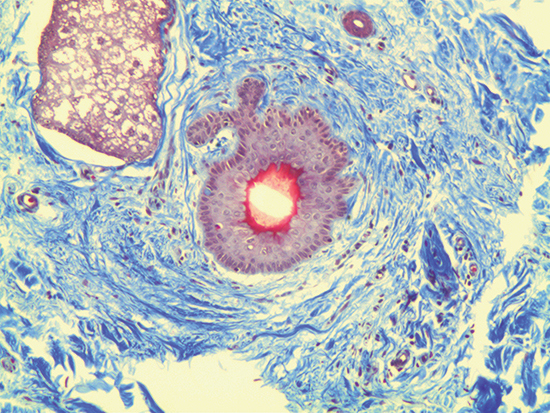

Figure 2 was captured using #59-877 10X M Plan Apo Objective. It has a numerical aperture of 0.28, field of view on a ½" sensor of 0.64mm x 0.48mm, and a resolving power of 1μm. In this image, it is clear to see the stacking and weaving of the ECM and interstitial structures. Additionally, the cellular membrane is very pronounced and it is evident that there are a number of intracellular structures such as ribosomes, mitochondria, and a large nucleus present at the central position.

Figure 2: Trichrome Stain of Dermal Tissue Samples at 10X Magnification Using #59-877 Objective